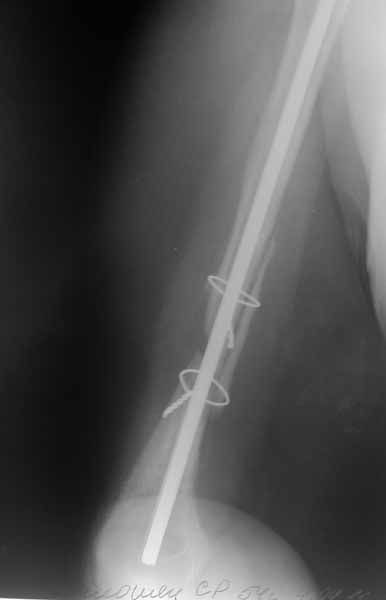

Плечевой сустав на сегодняший день спустя 10 мес. после травмы.

Такое впечатление, что здесь не вывих, но сублюксация головки из-за длительного вынужденного положения, обусловленного особенностью первичного остеосинтеза.

Согласен с Антоном Бехтеревым- здесь скорее всего имеет место выраженная атрофия дельт и как следствие подвывих головки плеча.

Согласен с коллегой в предположениях, однако склоняюсь к мысли, что имеем дело с нейропатией n. axillaris. Дело в том, что в случае обширного повреждения ВМП нижняя дислокация, как правило, не такая выраженная, т.к. нивелируется за счет тонуса дельтовидной мышцы. Ее вектор тяги направлен в сторону акромиона. Картина очень характерна для паралитической сублюксации. Работает ли дельта? Вы пишете, что пациентка активно зацималась ЛФК. Насколько активно можно заниматься при таком положении штифта? Вероятнее всего он выстоял кпереди от акромиона - это больно, а если под (на снимках не видно)то наличие каких-либо движений вообще сомнительно. Если дельтовидная мышца функционирует, напряжение ее волокон контурируется у худых и ощущается у полных даже при длительном бездействии. Кроме того наличие гипо- или анестезии в дельтовидной области поможет определиться. ЭНМГ прояснит ситуацию.